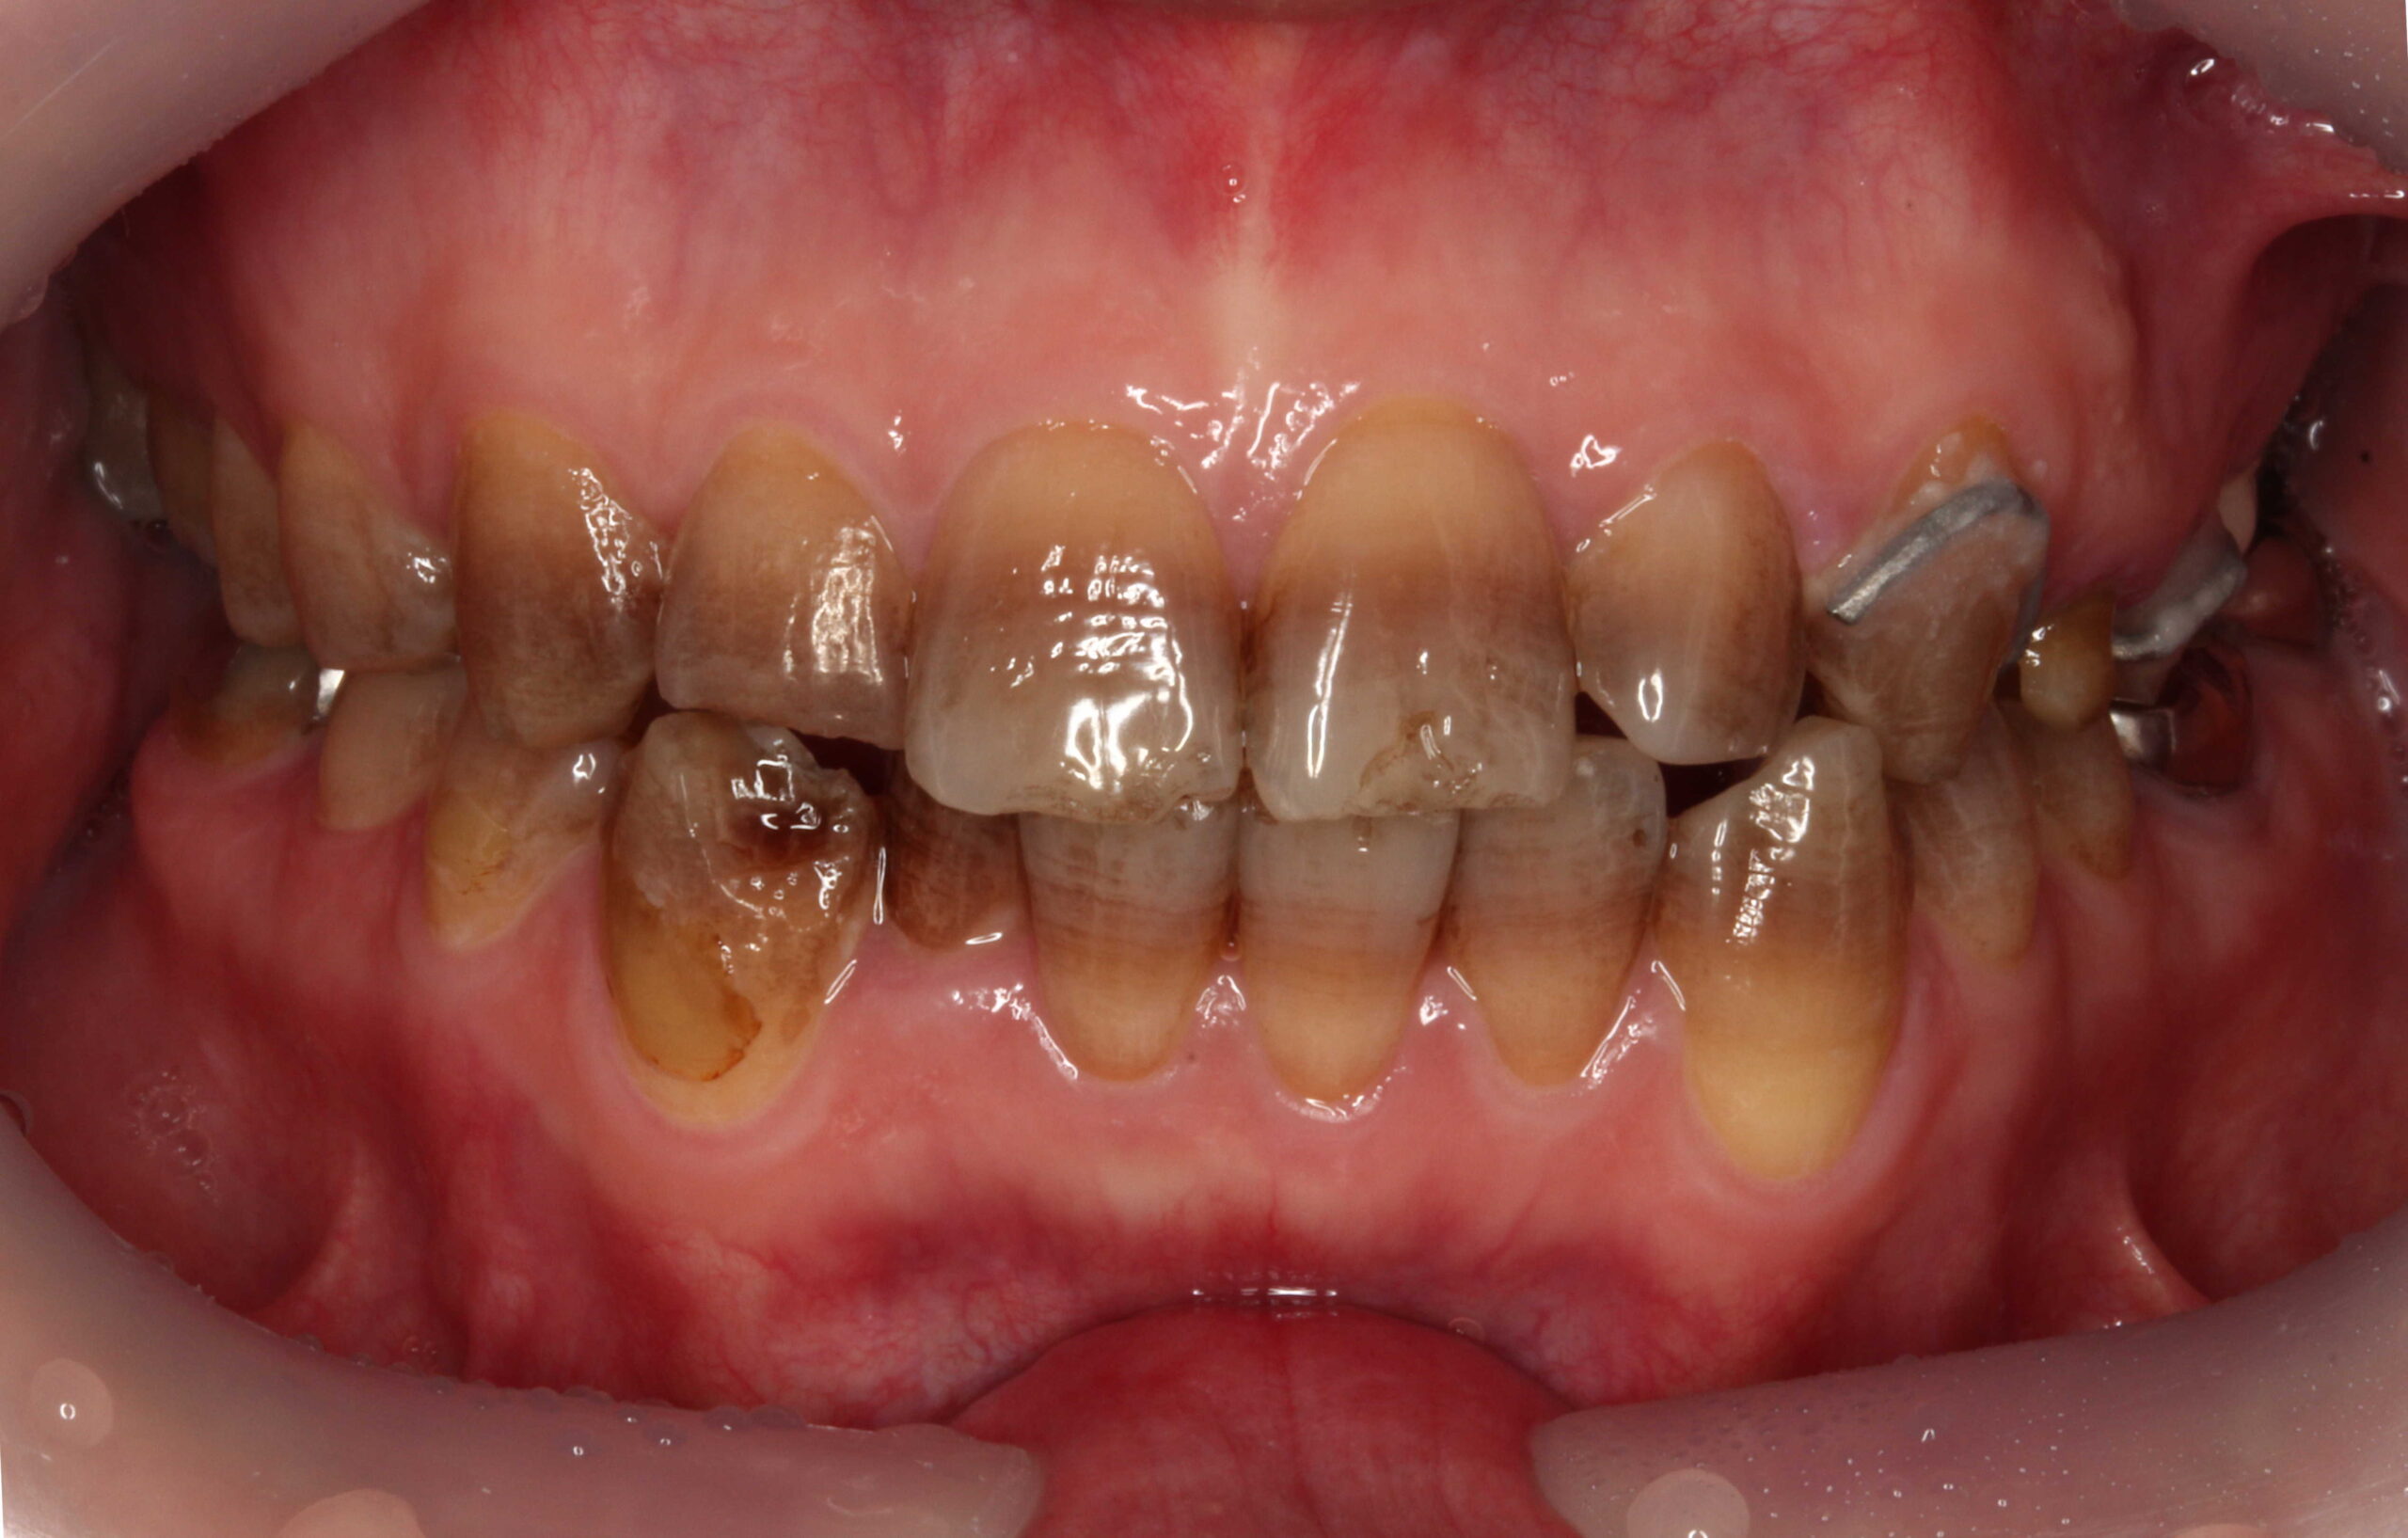

テトラサイクリン歯でホワイトニングをした事例

テトラサイクリン歯に対してもホワイトニングは一定の効果があります。

ホワイトニング前 ホワイトニング後

当院のホワイトニングは高品質で効果が高い製品なのですが、完全な白い歯にすることは難しいです。

削らないラミネートベニアは歯を削らないセラミックの審美歯科です。

なお、左上3は他院で治療中のため、歯のマニキュアのみ行っています。